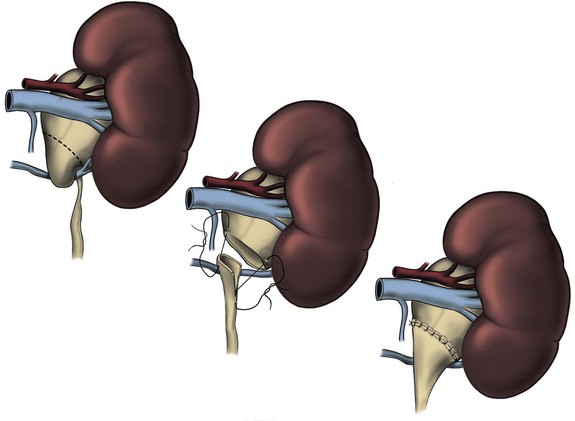

The initial transperitoneal approach to laparoscopic pyeloplasty was first described by Schuessler and colleagues (1993) and Kavoussi and colleagues (1993), and this approach has been the most widely used laparoscopic method due to its associated large working space and familiar anatomy. Before the laparoscopic portion of the procedure, cystoscopy with retrograde pyelography is first performed to define the anatomy and confirm the diagnosis, followed by placement of a ureteral stent and a urethral Foley catheter. The patient is placed in a 45-degree lateral decubitus position, and access to the peritoneal cavity is obtained via either the Veress needle or the Hassan access technique. Three to five laparoscopic ports are placed after the creation of CO2 pneumoperitoneum. Typically the umbilical port is for the laparoscope use. Colonic mobilization to expose the retropetioneal structures is the initial step of the laparoscopic procedure, although transmesenteric approach without bowel mobilization has been reported if renal pelvis or ureter can be readily recognized through the descending colonic mesentery (Romero et al, 2006). After medial mobilization of the colon, the ureter is identified and dissected in the cephalad direction to achieve mobilization of the ipsilateral proximal ureter, ureteropelvic junction, and renal pelvis (Fig. 41–13A). Extensive dissection of the ureter and excessive electrocautery use in close proximity to the ureter should be avoided to minimize injury to its vascular supply. At this time, the anatomy of the proximal ureter, renal pelvis, and nearby vasculature are carefully examined to determine the etiology of the ureteropelvic junction obstruction and the appropriate type of surgical repair. The general methods and principles of various types of surgical repair for laparoscopic pyeloplasty are identical to those described for open pyelplasty. If dismembered pyeloplasty is to be performed, which is suitable for the presence of crossing vessels, the renal pelvis is first transected circumferentially above the ureteropelvic junction and the lateral aspect of the proximal ureter is spatulated (Fig. 41–13B). The renal pelvis and proximal ureter are then transposed to the opposite side of the crossing vessel, if such vessel is present, and the ureteropelvic anastomosis is then completed with intracorporeal suturing techniques (Fig. 41–13C-D). In the presence of redundant renal pelvis, reduction pelvioplasty may be performed by excising redundant renal pelvic tissue and closing the pyelotomy. The actual laparoscopic suturing maneuver can be accomplished either freehand or with a semiautomated device (EndoStitch, US Surgical, Newark, CT). Either continuous running or simple interrupted suturing method may be used in the dismembered laparoscopic pyeloplasty, typically with the 4-0 absorbable suture. A surgical drain is placed after the completion of the anastomosis, and one of the trocar sites is typically used as the drain exit site.

Figure 41–13 A, Transperitoneoscopic view of a patient with left pyelplasty. The patient’s head is to the left. Note the proximal ureter is sandwiched between an anterior crossing lower pole renal artery (wrapped with white vessel loop and retracted upward) and a posterior crossing lower pole vessel (wrapped with white vessel loop). The suction-irrigator tip points at the left ureteropelvic junction. B, The left proximal ureter is being transected with laparoscopic scissors, revealing the preplaced ureteral stent within the ureteral lumen. C, The ureteral stent is transposed anterior to the anteriorly crossing vessel following circumferential transection of the proximal left ureter. D, Ureteropelvic anastomosis is completed with intracorporeal suturing techniques.